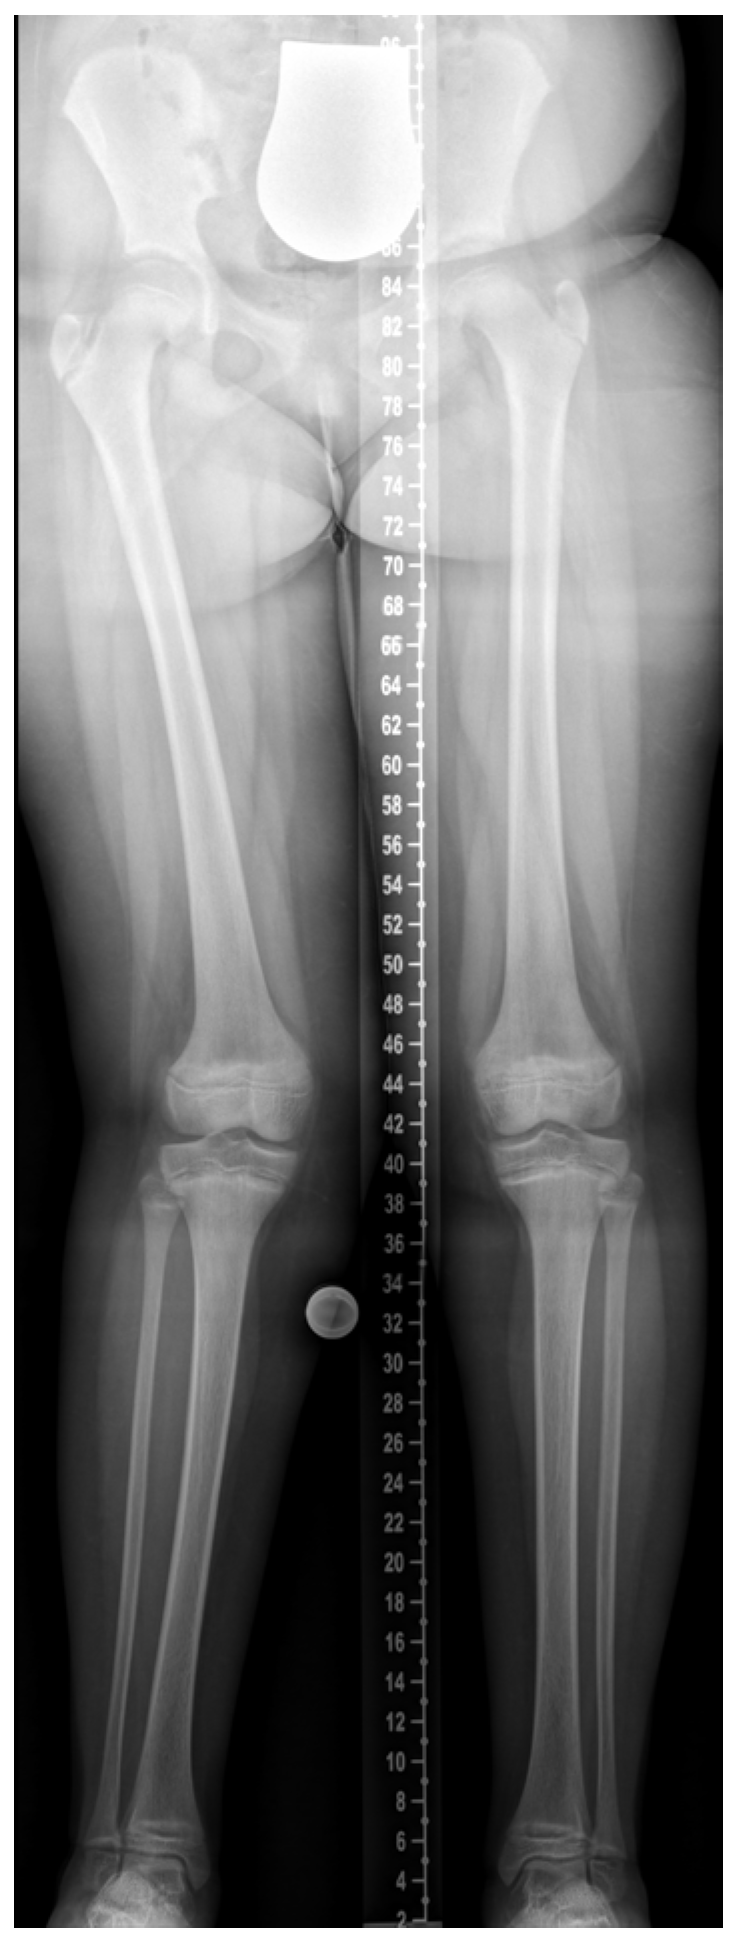

Skeletal deformities, particularly of the lower limbs, are hallmark manifestations of rickets and sometimes the first signs prompting clinical evaluation. Coronal plane deformities such as genu varum and genu valgum are well recognized, but recent imaging and gait analysis studies—especially in XLH—highlight more complex multiplanar deformities involving the sagittal (e.g., femoral or tibial procurvatum) and axial planes (e.g., femoral torsion, tibial torsion), as well as pelvic malalignment [10,11,12,13,14]. Clinical cases may present with asymmetric or combined deformities, as illustrated in Figure 2. These deformities can contribute to pathological gait patterns, recurrent falls, pain, early-onset joint degeneration, and impaired quality of life [15,16,17].

Figure 2. A 10-year-and-10-month-old girl with nutritional rickets. Radiographic findings show valgus deformity of the right leg and varus deformity of the left leg (windswept deformity). Image courtesy of Dr. Gabriel T. Mindler, Department of Pediatric Orthopedics, Orthopedic Hospital Speising, Vienna, Austria.